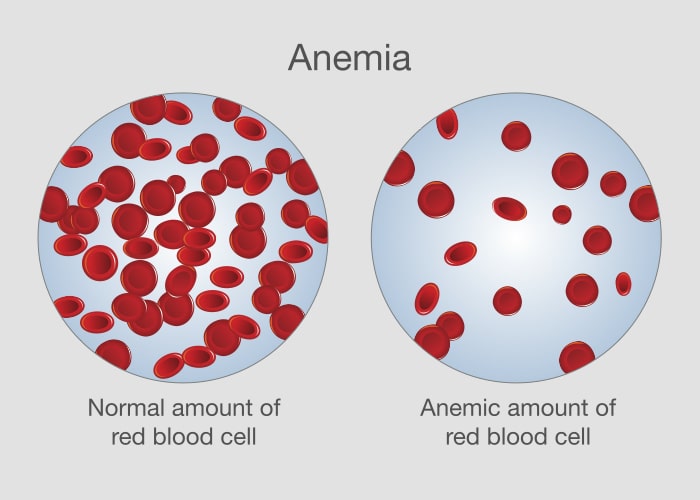

Ciąża to czas ogromnych zmian w ciele kobiety, nie tylko na poziomie hormonalnym, ale także w zakresie zapotrzebowania dotyczącego składników odżywczych. Jednym z często występujących stanów, który może mieć wpływ na zdrowie matki i rozwijającego się dziecka, jest anemia. Zrozumienie tego, czym jest anemia w ciąży, jakie są jej przyczyny, objawy oraz metody leczenia, jest kluczowe dla zapewnienia zarówno matce, jak i dziecku optymalnych warunków zdrowotnych.

Warto zaznaczyć, że oprócz niedoborów żelaza, witaminy B12 i kwasu foliowego, istnieją również inne czynniki, które mogą przyczyniać się do rozwoju anemii. Na przykład, choroby przewlekłe, takie jak choroby nerek, choroby autoimmunologiczne lub cukrzyca, mogą wpływać na produkcję hemoglobiny i zdolność organizmu do prawidłowego wykorzystania żelaza. Ponadto, infekcje czy przewlekłe stany zapalne również mogą zaburzać homeostazę żelaza, prowadząc do anemii.

Znaczącym aspektem jest też fakt, że anemia może wynikać z genetycznych predyspozycji do zaburzeń takich jak talasemia czy anemia sierpowata, które mogą ujawnić się lub nasilić podczas ciąży. Ważne jest również zwrócenie uwagi na dietę kobiety ciężarnej, która może nie dostarczać wystarczającej ilości żelaza lub innych kluczowych składników odżywczych, jeśli jest niezbilansowana lub oparta na ściśle wegetariańskiej lub wegańskiej diecie bez odpowiedniej suplementacji.

Podsumowując, anemia w ciąży wymaga kompleksowego podejścia, uwzględniającego zarówno dietę i suplementację, jak i analizowanie stanu zdrowotnego. Zrozumienie i rozpoznanie przyczyn anemii jest pierwszym krokiem do skutecznego zapobiegania i leczenia tego stanu, co jest niezbędne dla zapewnienia optymalnych warunków do rozwoju płodu oraz utrzymania zdrowia matki.

Zrozumienie roli hemoglobiny w kontekście ciąży jest niezbędne dla zapewnienia odpowiedniej opieki nad zdrowiem matki i rozwijającego się dziecka. Hemoglobina nie tylko odgrywa kluczową rolę w transporcie tlenu, ale także w prawidłowym rozwoju płodu. Niski poziom hemoglobiny może wpływać na dostarczanie tlenu do komórek i tkanki płodu, co ma zasadnicze znaczenie dla jego wzrostu i rozwoju.